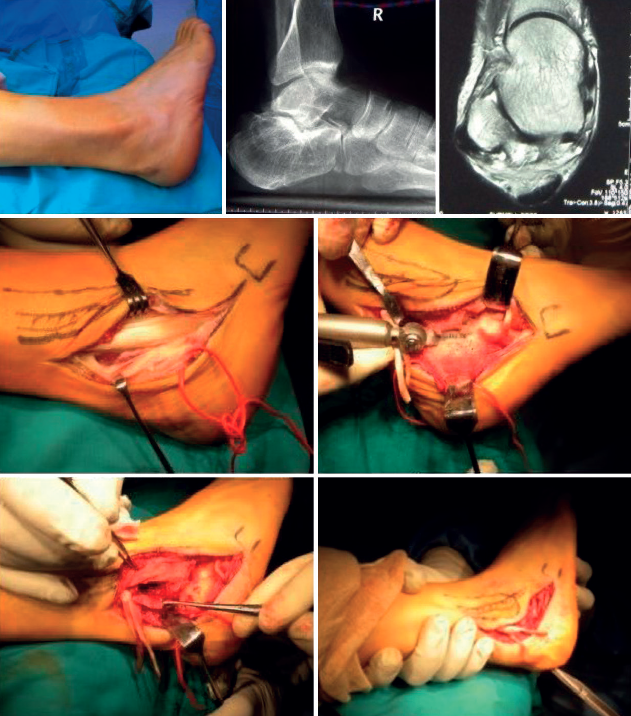

En el caso de las lesiones de tipo II, caracterizadas por el desgarro de un tendón asociado con un tendón restante con una excursión adecuada, clásicamente se ha sugerido que, si la rotura afecta a menos del 50% del tendón una vez desbridado, este puede ser reparado mediante tubulización (Figura 7), pero si afecta a más del 50% debe realizarse una tenodesis(39). Según la ESSKA esta recomendación es arbitraria y no está basada en la evidencia. Es mejor reparar un tendón, siempre que una vez reparado resista a la tracción ejercida por el cirujano(8). Se han publicado buenos resultados en cuanto a escalas de valoración, así como de vuelta a la actividad física(15,37,40).

Por el contrario, Danna y Brodsky, basándose en sus observaciones, justifican realizar la escisión del corto (cuando la rotura afecta a más del 50%) y su tenodesis al largo, porque el tendón del músculo corto reparado suele acabar adherido al PL, causando dolor debido a la restricción de la excursión del tendón(39).

Inicialmente, se recomienda el tratamiento conservador y, aunque hasta un 50% puede presentar recurrencia, el tratamiento quirúrgico secundario no presenta peores resultados ni modifica las posibilidades quirúrgicas(8). Las opciones quirúrgicas son la reducción de los tendones, la reparación directa del RPS y la profundización del surco retromaleolar, que se pueden realizar tanto de forma abierta como endoscópica.

En el caso de cirugía abierta, se realiza la reparación directa del retináculo(54). No existe consenso sobre si es necesario asociar la profundización del surco en pacientes no deportistas(8). Es importante no dejar en excesiva tensión el RPS para no provocar conflictos de espacio. Si optamos por el tratamiento endoscópico, se recomienda realizar un desbridamiento del borde lateral y asociar la profundización del surco retromaleolar, siendo la reparación del RPS opcional. El uso de anclajes óseos y nudos se puede relacionar con irritación y dolor, sobre todo en zonas con escaso tejido subcutáneo, por lo que se han diseñado técnicas sin nudos(55).

Lesiones agudas en atletas

El tratamiento de elección es quirúrgico. En atletas sí se recomienda incluir profundización del surco retromaleolar. Tanto el tratamiento abierto como el endoscópico son correctos. El tratamiento endoscópico presenta menores tasas de complicación y una reincorporación al deporte más precoz(38,56).